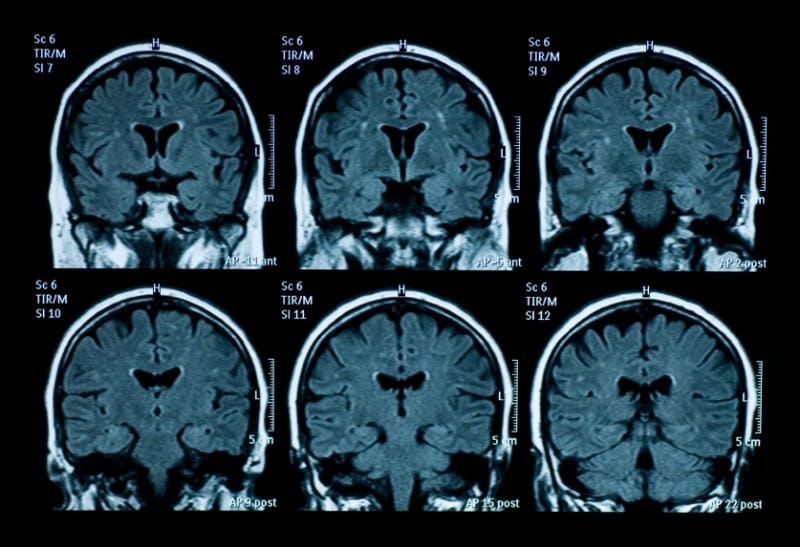

A Chinese study reveals that individuals addicted to the web have similar brain scans to drug abusers and other addicts. Moreover, these scans correlate with British scientists’ findings on those addicted to videogames.

Special MRI scans revealed that white matter in the brains of web addicts, specifically within the nerve fibers connecting areas of the brain that control emotion, decision-making, and self-control.

For the first time two studies show changes in the neuronal connections between brain areas as well as changes in brain function in people who are frequently using the internet or video games.